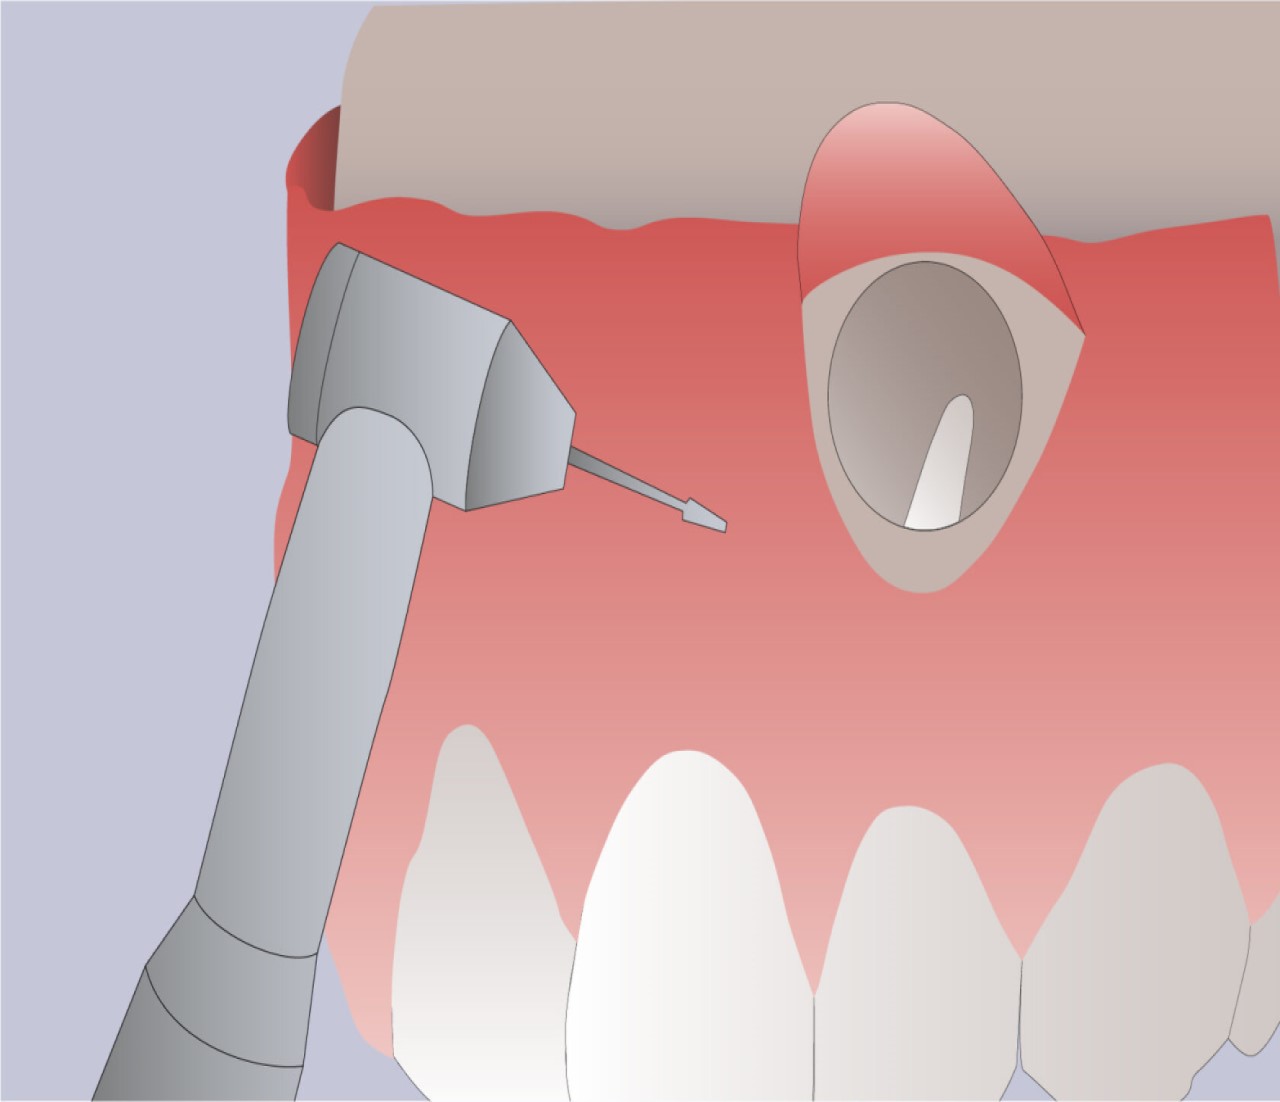

Резекция верхушки корня

Резекция верхушки корня зуба – это зубосохраняющая операция с удалением верхней части зубного корня